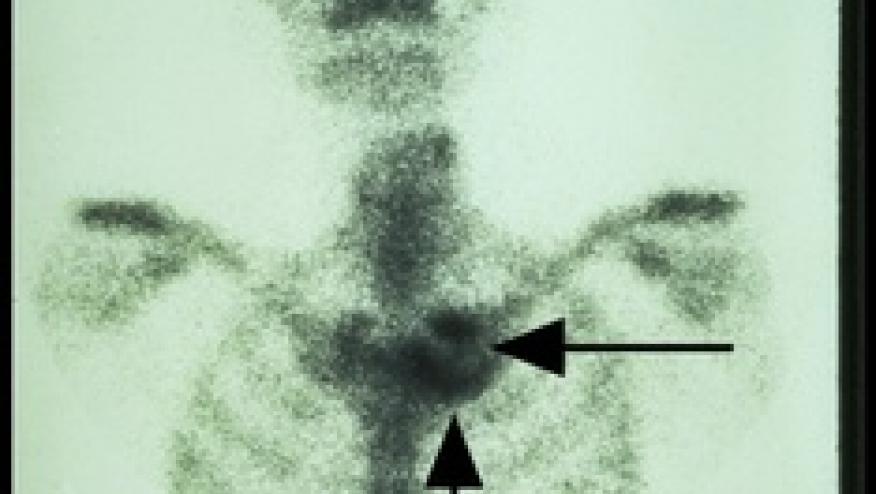

A EULAR task force of 21 rheumatologists and radiologists from 11 countries examined 12 clinical/imaging questions and reviewed the literature to establish consensus on imaging for spondyloarthritis in practice. For axial SpA, conventional radiographs should be used first, but MRI may be used in young patients, new-onset patients or when the diagnosis is suspected and X-rays are negative.